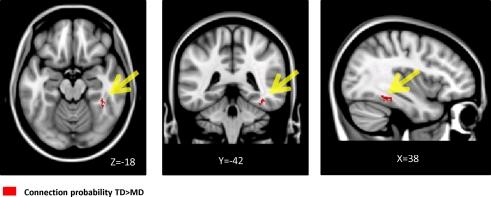

Poor mathematical abilities adversely affect academic and career opportunities. The neuroanatomical basis of developmental dyscalculia (DD), a specific learning deficit with prevalence rates exceeding 5%, is poorly understood. We used structural MRI and diffusion tensor imaging (DTI) to examine macro- and micro-structural impairments in 7- to 9-year-old children with DD, compared to a group of typically developing (TD) children matched on age, gender, intelligence, reading abilities and working memory capacity. Voxel-based morphometry (VBM) revealed reduced grey matter (GM) bilaterally in superior parietal lobule, intra-parietal sulcus, fusiform gyrus, parahippocampal gyrus and right anterior temporal cortex in children with DD. VBM analysis also showed reduced white matter (WM) volume in right temporal-parietal cortex. DTI revealed reduced fractional anisotropy (FA) in this WM region, pointing to significant right hemisphere micro-structural impairments. Furthermore, FA in this region was correlated with numerical operations but not verbal mathematical reasoning or word reading. Atlas-based tract mapping identified the inferior longitudinal fasciculus, inferior fronto-occipital fasciculus and caudal forceps major as key pathways impaired in DD. DTI tractography suggests that long-range WM projection fibers linking the right fusiform gyrus with temporal-parietal WM are a specific source of vulnerability in DD. Network and classification analysis suggest that DD in children may be characterized by multiple dysfunctional circuits arising from a core WM deficit. Our findings link GM and WM abnormalities in children with DD and they point to macro- and micro-structural abnormalities in right hemisphere temporal-parietal WM, and pathways associated with it, as key neuroanatomical correlates of DD.

较差的数学能力会对学业和职业机会产生不利影响。发育性计算障碍(DD)是一种特定的学习障碍,患病率超过5%,但其神经解剖学基础仍知之甚少。我们使用结构磁共振成像(MRI)和扩散张量成像(DTI)来检查7至9岁DD儿童的宏观和微观结构损伤,并与一组在年龄、性别、智力、阅读能力和工作记忆能力方面相匹配的正常发育(TD)儿童进行比较。基于体素的形态计量学(VBM)显示,DD儿童双侧顶上小叶、顶内沟、梭状回、海马旁回和右侧颞前皮质的灰质(GM)减少。VBM分析还显示右侧颞顶叶皮质的白质(WM)体积减少。DTI显示该WM区域的分数各向异性(FA)降低,表明右侧半球存在明显的微观结构损伤。此外,该区域的FA与数字运算相关,但与言语数学推理或单词阅读无关。基于图谱的纤维束映射确定了下纵束、额枕下束和主要的尾侧钳状束是DD中受损的关键通路。DTI纤维束成像表明,连接右侧梭状回与颞顶叶WM的长程WM投射纤维是DD中一个特定的易损源。网络和分类分析表明,儿童DD可能以核心WM缺陷引起的多个功能失调回路为特征。我们的研究结果将DD儿童的GM和WM异常联系起来,并指出右侧半球颞顶叶WM及其相关通路的宏观和微观结构异常是DD的关键神经解剖学相关因素。